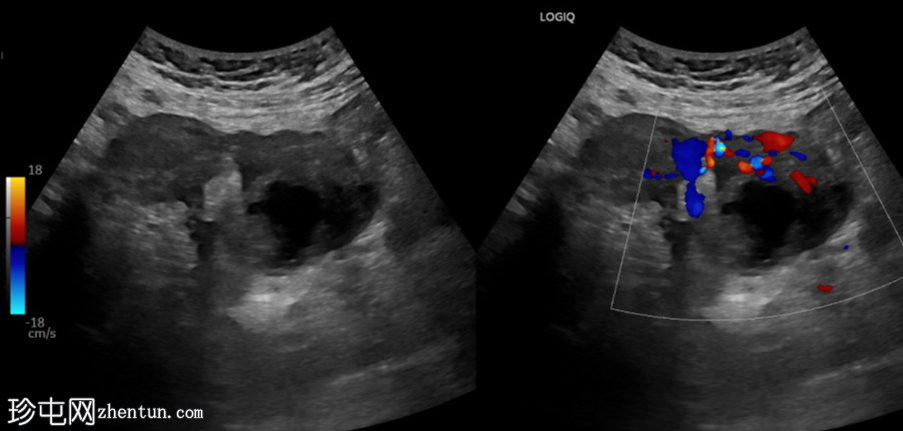

超声检查

横切面

左侧卵巢明显增大,可见一囊肿,大小约3.2 x 2.3 cm,呈火环征,可能为黄体囊肿。左侧卵巢与子宫之间可见一管状结构,直径约1.3 cm,内含浑浊液体,未见血管,最可能为输卵管积血。以上特征提示可能为左侧异位妊娠。

未见宫内妊娠囊。

95%的异位妊娠着床于输卵管,尤其是壶腹部。异位妊娠最有用的体征是卵巢以外的附件区出现不均匀病变,并伴有妊娠试验阳性。大多数异位妊娠发生较早,在卵黄囊或胚胎发育之前。腹腔内游离液体是破裂的征象。